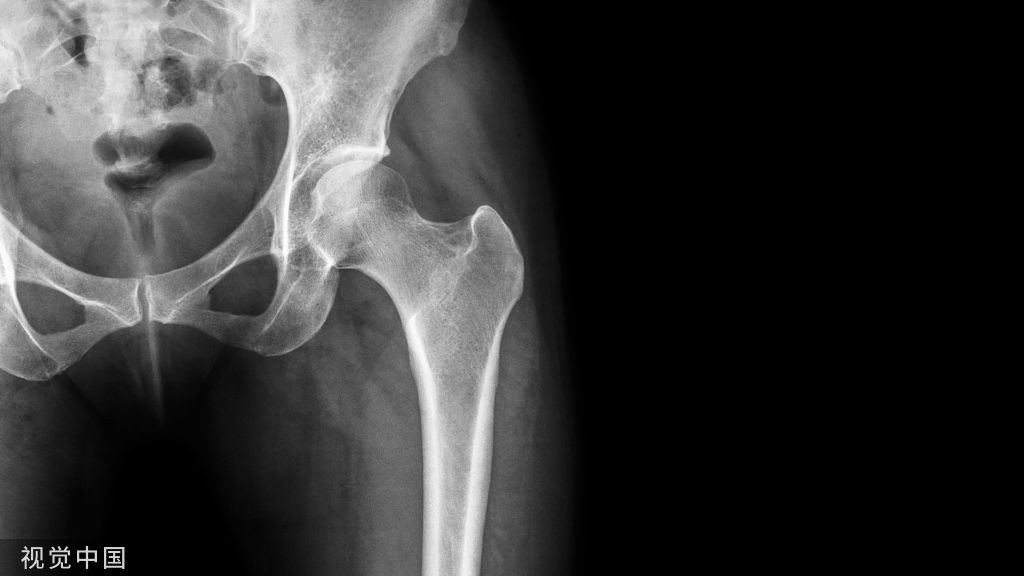

推荐意见 2:开放性骨折慎用高压冲洗,可使用 12 PSI 作为开放性骨折伤口冲洗的标准。(证据等级:A级;推荐强度:一般)